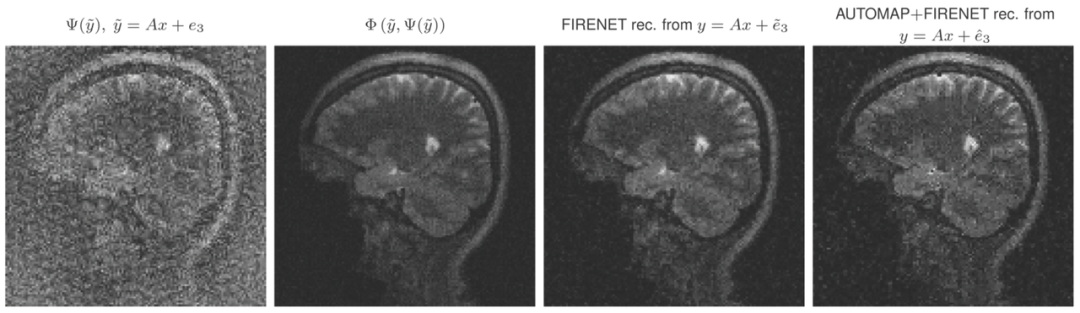

FIRENETs的稳定器作用

同时,FIRENETs也起到了一个稳定器的作用。比如在下图中,将来自AUTOMAP的重建输入到FIRENETs,结果显示,FIRENETs修正了AUTOMAP的输出并将重建加以稳定化。

图注:在AUTOMAP 的末端添加一些FIRENET层使其稳定。最左边是AUTOMAP的重建。左二是x0 = Ψ( ̃y)的FIRENET 的重建。右二是 ̃y = Ax + e3时FIRENET 的重建。最右边是输入AUTOMAP 的测量值后FIRENET的重建。